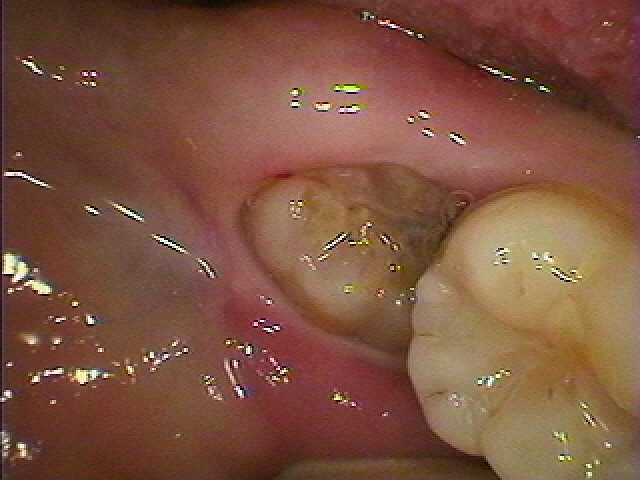

右下親知らずの抜歯 気を付けないと手前の歯にも虫歯が、、、|お知らせ |広島市安佐南区の歯科医院 右下親知らずの抜歯 気を付けないと手前の歯にも虫歯が、、、 トップ お知らせ・ブログ お知らせ 右下親知らずの抜歯 気を付けないと手前の歯にも虫歯が、、、 右下親知らずの抜歯 気を付けないと手前の歯にも虫歯が、、、 長い間このままになっていた親知らずになります 手前の歯が虫歯になっています 接触している手前の歯が黒く虫歯となっています この歯を抜歯していきます 手前の歯につっかえていてこれ以上萌えてこない歯になっていました 分割し抜歯しています 縫合して終了となります 余分な切開を加えてはいません 最小限の信州による抜歯かと思います Web診療予約 初めての方へ 選ばれ続ける理由 院内設備について 歯が痛いしみる一般歯科 歯がぐらぐらする歯周病 健康な歯を保ちたい予防歯科 子供の虫歯予防をしたい小児歯科 銀歯をセラミックに審美歯科 白い歯を目指しませんか?ホワイトニング 矯正専門医がいるので安心矯正歯科 抜けた歯を補いたいインプラント・入れ歯 医院案内 スタッフ紹介 メリィハウス歯科クリニックオフィシャルホームページ ラベンダー歯科クリニックオフィシャルホームページ お知らせ・ブログ ホーム 診療科目 一般歯科 歯周病治療 予防治療 小児歯科 審美治療 ホワイトニング 矯正歯科 入れ歯・インプラント マウスピース矯正 初めての方へ 院長・スタッフ 設備紹介 医院案内・アクセス メニューを閉じる